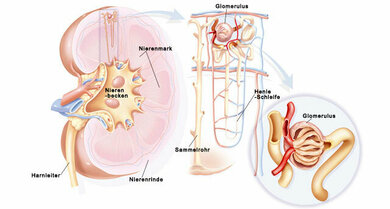

Niere und Glomeruli

Aufbau der Niere

Die Niere besteht aus Nierenrinde, Nierenmark und Nierenbecken. In der Nierenrinde liegen die sogenannten Nierenkörperchen. Hier findet ein Teil der Filterarbeit der Niere statt: Verschiedenste Stoffe sowie eine Menge Flüssigkeit verlassen dort in kleinen Gefäßknäuel, den sogenannten Glomeruli, zunächst die Blutgefäße und gelangen als sogenannter Primärharn in die Tubuli, wie die kleinen Harntransportwege heißen. Diese Tubuli münden in die im Nierenmark liegende Henle-Schleife. In Tubuli und Henle-Schleife erfolgt eine Art Feinabstimmung des Harns: Ein großer Teil der zunächst aus den Blutgefäßen herausgefilterten Flüssigkeit sowie andere Stoffe wie Kalium und Natrium werden je nach Bedarf des Körpers wieder aus dem Primärharn entfernt und in den Körper aufgenommen, andere Stoffe wiederum werden hinzugefügt, bis der fertige Harn entstanden ist und über die Sammelrohre und Nierenkelche ins Nierenbecken gelangt.